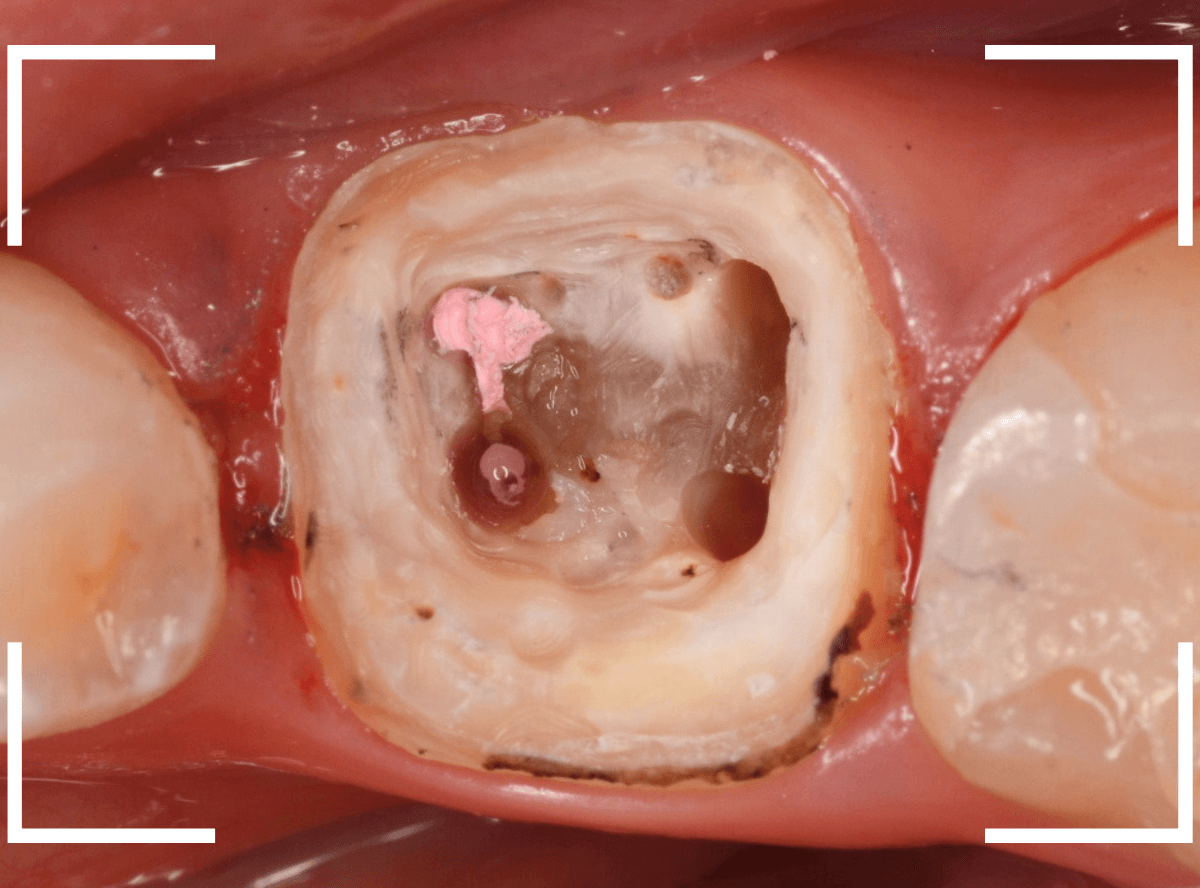

さし歯の土台の補修と、おやしらずの虫歯の処置をしたところです。

この状態で型をとります。

奥歯は歯に優しいファイバー・コアで再製し、型取りします。

模型上で精密に製作します。